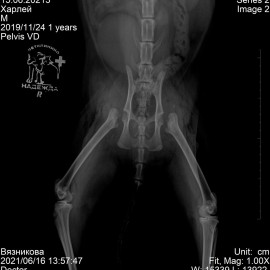

Было проведено рентгенологическое исследование, в ходе которого был выявлен эпифизиолиз головок правого и левого бедра.

Снимок до операции.